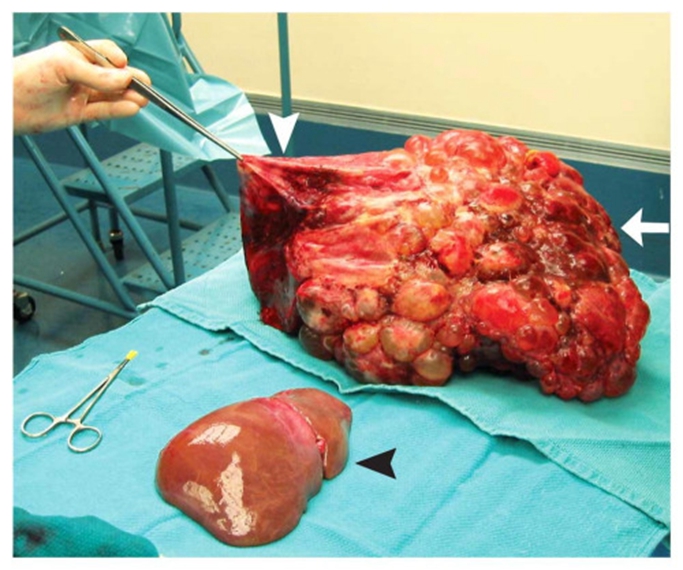

_原發性肺纖維化晚期

_重度肺纖維化的晚期

_重度肺纖維化晚期症狀